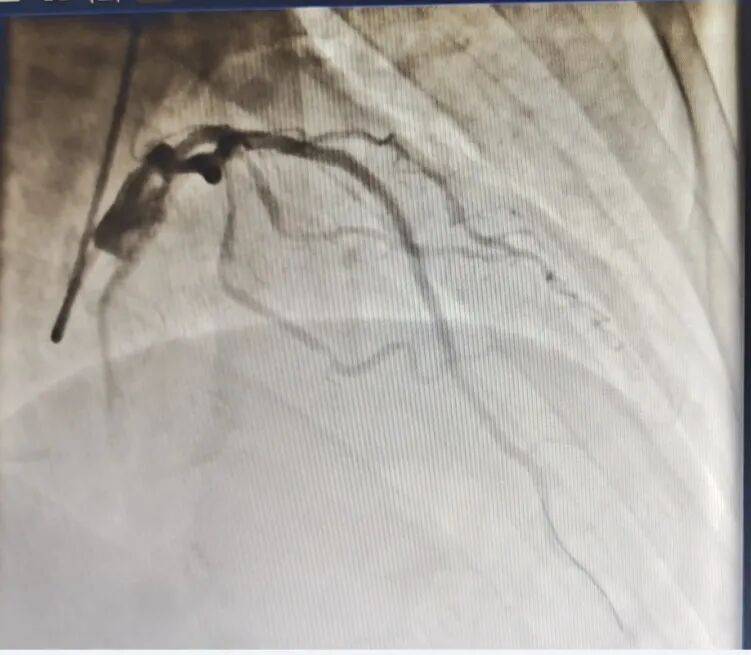

然而,病情远比想象的复杂。造影显示,患者心脏多支血管严重病变,血流细若游丝。医疗团队决定先行稳定,计划一周后手术。

▲ 血管开通前